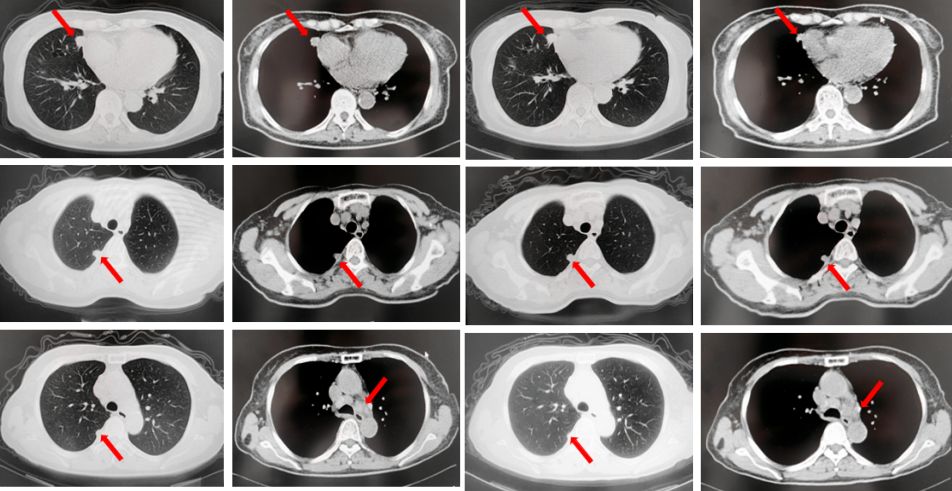

2022年7月至2022年11月行贝伐珠单抗联合培美曲塞/顺铂方案治疗6周期,2周期后评效PR,4周期后评效SD-(如图1)。第6周期治疗结束后患者自行终止治疗。

图1:由左至右分别展示基线(A.)及一线治疗后改变(B.和C.)。红色箭头指示病灶位置,由上至下分别为右肺肿物、右侧胸膜转移病灶及胸腔积液、左侧胸膜转移病灶、多发纵隔淋巴结肿大。

2023年3月患者因咳嗽伴胸闷复查出现全面PD。2023年3月-2023年4月重启原方案贝伐珠单抗联合培美曲塞/顺铂治疗2周期。2023年5月复查评效PD。行左锁骨上淋巴结穿刺,病理回报:左锁骨上见异型细胞,考虑为癌可能性大。组织NGS基因检测:MET基因扩增(变异倍数)2.0倍,TP53错义突变,PD-L1(22C3):TPS 75%。2023年5月-2023年8月改行替雷利珠单抗联合紫杉醇脂质体治疗4周期,2周期后评效SD。(如图2)

图2:A.代表一线治疗停药后病情进展,右肺上叶肿物、右侧胸膜转移灶及纵隔淋巴结较前增大、增多,右侧胸腔积液较前增多;B.原方案重启后复查评效右肺上叶肿物及纵隔淋巴结较前略饱满,右侧胸腔积液较前明显增多;C.更改二线治疗方案后整体病灶较前无显著变化。

2023年9月复查评效PD。成功入组“一项开放、多中心对比谷美替尼与多西他赛在既往接受免疫治疗和含铂双药化疗后进展的驱动基因阴性且伴有MET扩增的局部晚期或转移性非小细胞肺癌患者中的随机对照III期临床研究”。成功随机到试验组,口服谷美替尼至2024年10月,期间复查最佳评效PR。

图3:A.二线治疗后病情进展,右肺上叶新发肿物较前明显增大,新发无症状脑转移病灶;B.经谷美替尼(300mg po qd)治疗3个月后复查肺内病灶及颅内病灶较前明显缓解